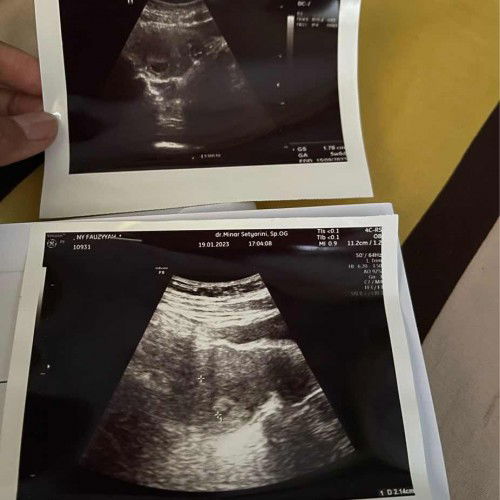

Usg 5w beda hasil

Halo bun , mau sharing dong .. Aku HPHT 14 desember usia khamilan hrusnya brpa ya ?? Ini aku 2x usg di doktr yg berbeda . Yg atas katanya bru ada kantung usia 5w. Yg bawah usg katanya belum terlihat GS nya . Bingung bun yg bener yg mana ya? Memang di usg yg bawah itu doktr cuma sebentr usg nya ga trlalu di cari . Yg usg atas doktr agak lama cari nya . Apa mugkn krna aku rahim retro jdi ga trlalu kliatan ya bun di usg yg bawah itu .

Read more